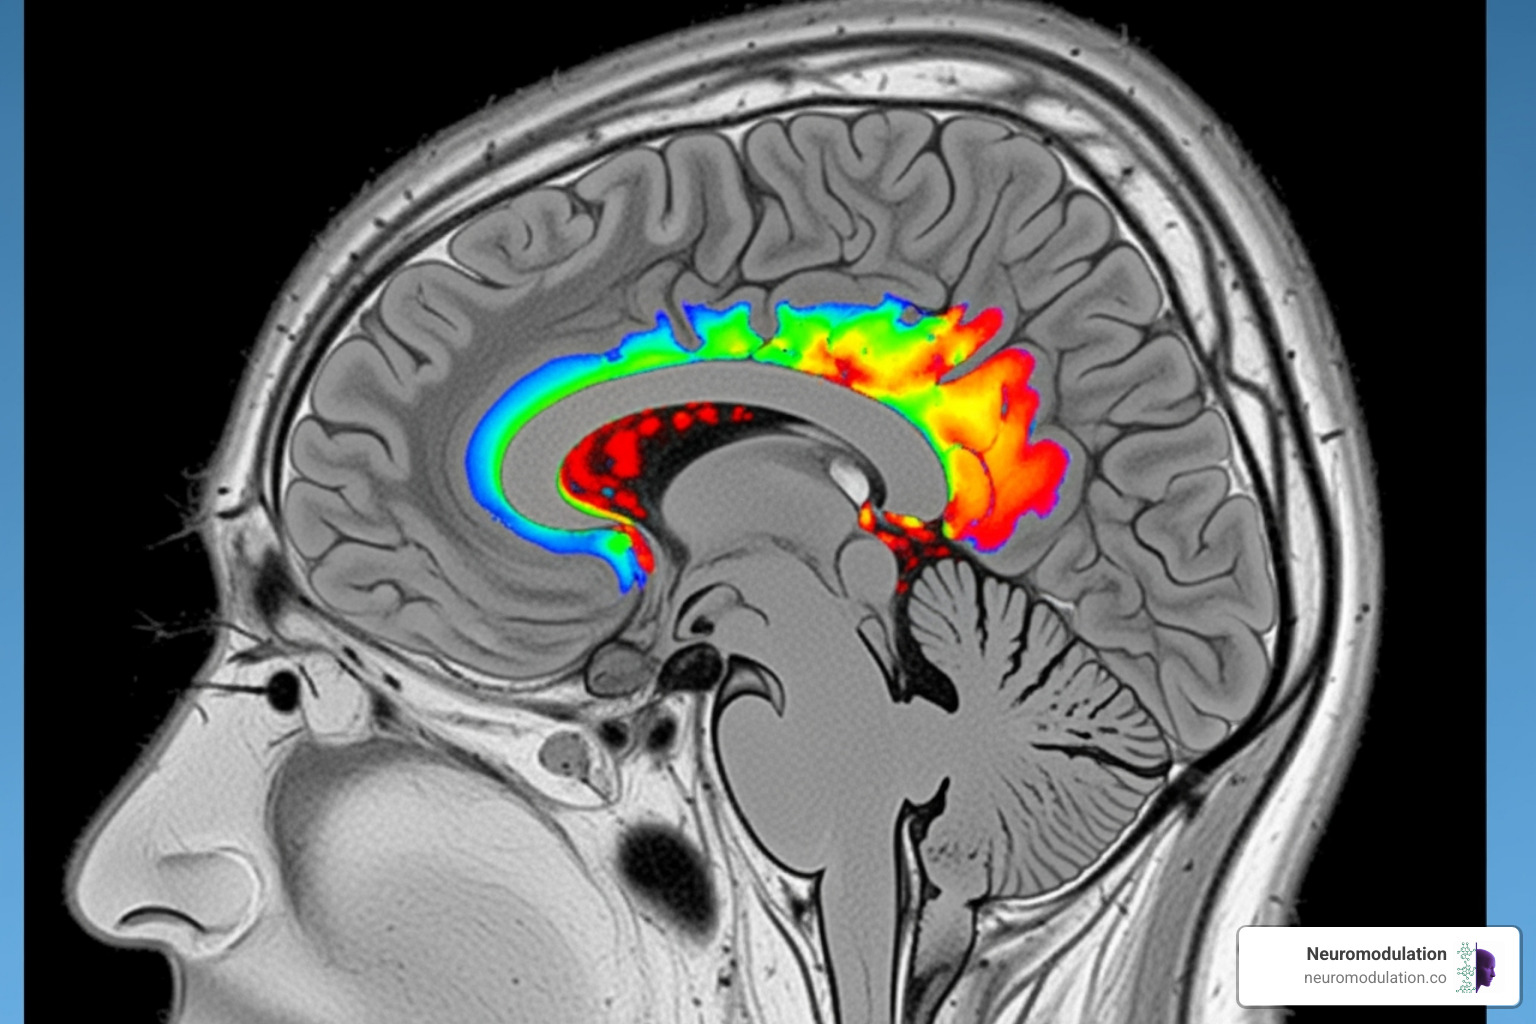

CED works by directly infusing therapeutic agents into the brain’s interstitial space (the fluid-filled gaps between cells). Instead of slow diffusion, CED uses gentle, continuous pressure to actively push medication through brain tissue. This “bulk flow” distributes drugs much farther and more uniformly. While diffusion might move a drug millimeters, CED can distribute medications centimeters deep, creating high local concentrations with minimal systemic side effects. For technical details, A review of CED mechanisms offers an in-depth explanation.

The CED process starts with precise MRI or CT imaging to map the target area. During the procedure, neurosurgeons insert ultra-thin catheters into the brain. These catheters are connected to a specialized pump that creates a positive pressure gradient, gently pushing the liquid medication into the brain tissue at a controlled flow rate (typically 0.1 to 10 microliters per minute). This ensures optimal distribution over large, clinically relevant volumes without causing tissue damage.